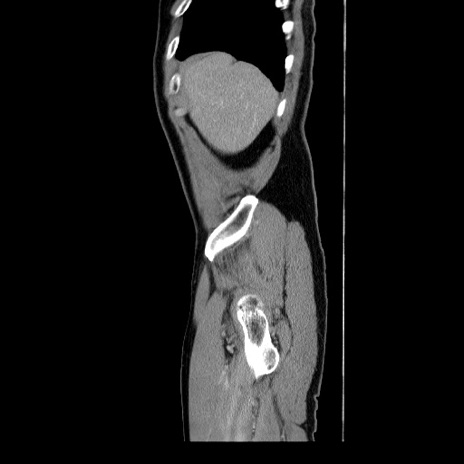

症例34(矢状断像)

【症例】60歳代 男性

【主訴】右鼠径部膨隆

【現病歴】1年程前より右鼠径部膨隆あり。自己にて還納可能だったため放置していた。3時間前より右鼠径部の脱出を認め、還納困難となり受診。

【身体所見】右鼠径部に小児頭大の膨隆あり。弾性硬であり、用手還納は困難。左鼠径部にも膨隆を認める。脱出はなし。